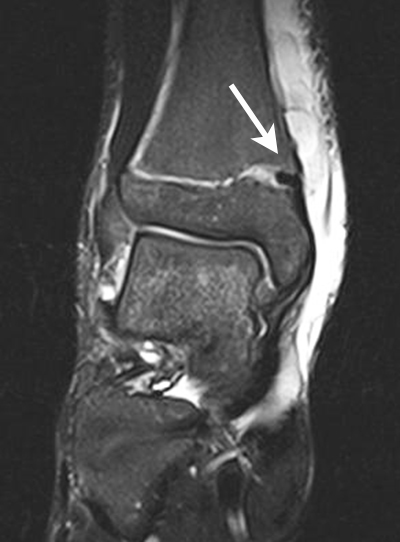

Übergangsfrakturen

Übergangsfrakturen sind spezielle Verletzungen, die ausschließlich in der Lebensphase beobachtet werden, in welcher die Wachstumsfugen teilweise geschlossen sind. Die Wachstumsfuge an der distalen Tibia schließt sich von ventromedial beginnend nach dorsal und lateral. Während die bereits geschlossene Wachstumsfuge eine hohe Stabilität aufweist, ist der knorpelige Anteil der noch offenen Fuge wesentlich weniger widerstandsfähig. Die mechanisch schwächste Schicht der Wachstumsfuge ist der Blasenknorpel. Durch Biege- und Scherkräfte kommt es zu einer Verletzung der Wachstumsfuge mit Aussprengung eines metaphysären Keils. Übergangsfrakturen sind „unvollendete“ Fugenschaftfrakturen bei welchen die bereits geschlossene Fuge ein Auslaufen der Frakturlinie durch die Fuge verhindert und daher die Bruchlinie ins Gelenk ausläuft (v. Laer 2013).

Rein epiphysäre Frakturen werden als Twoplane-Frakturen bezeichnet. Der Frakturverlauf liegt in der Epiphyse und dem noch nicht verknöcherten Anteil der Wachstumsfuge. Gibt es noch einen zusätzlichen metaphysären Keil handelt es sich um eine Triplane-Fraktur. Bei einer Triplane-Fraktur kann sich in Einzelfällen die metaphysäre Fraktur bis in die Epiphyse fortsetzen, sodass eine zusätzliche Querfraktur resultiert. Es entsteht der Eindruck eines zusätzlichen hinteren Volkmann Fragments.

• Twoplane-Fraktur: Epiphysäre Fraktur, welche epiphysär und durch den noch nicht verknöcherten Teil der Fuge verläuft (Aitken II Verletzung bei einer teilweise mineralisiert Wachstumsfuge).

• Triplane-I-Fraktur: Epiphysäre Fraktur, mit teilweisem Verlauf durch die Wachstumsfuge und gleichzeitigem metaphysären Keil.

• Triplane-II-Fraktur: Epiphysäre Fraktur, mit Verlauf durch die Wachstumsfuge. Der metaphysäre Keil setzt sich in die Epiphyse fort, was zu einer weiteren quer verlaufenden Frakturlinie im Gelenk führt.

In Abhängigkeit vom Reifezustand der Wachstumsfuge kann der epiphysäre Frakturspalt sehr weit medial bis ganz lateral zu liegen kommen. Ein sehr weit lateral liegender Frakturspalt entspricht funktionell nahezu einem knöchernen Ausriss der vorderen Syndesmose, was sich im Röntgenbild an einer erweiterten Malleolengabel erkennen lässt 9

Der teilweise komplexe Frakturverlauf bei Übergangsfrakturen lässt sich im CT zuverlässig darstellen 10. Der erfahrene Untersucher kann bereits mit Röntgenaufnahmen des Sprunggelenks in zwei Ebenen in Verbindung mit zwei 45° Schrägaufnahmen sehr umfassende Aussagen zum Frakturverlauf treffen (v. Laer 2013), die Präzision und Aussagekraft der Computertomografie ist aber zweifelsohne überlegen und wird von den meisten Behandlern bevorzugt 11, auch wenn sich zu diesem Thema in der Literatur eine teilweise sehr emotional geführte Diskussion findet. Einigkeit hinsichtlich der Indikation für ein Schnittbildverfahren besteht bei Triplane-Frakturen, wenn Zweifel darüber bestehen, inwieweit die metaphysäre Fraktur den tragenden Gelenkanteil tangiert 12.